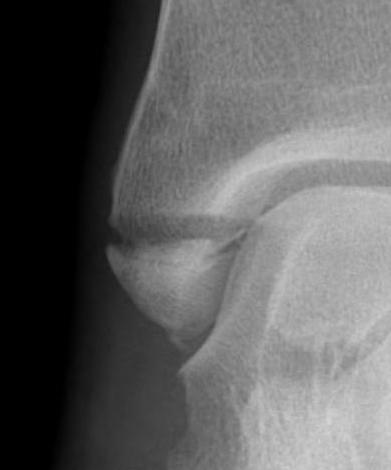

![]() |

Screw fixation

AO surgery reference medial malleolus lag screws